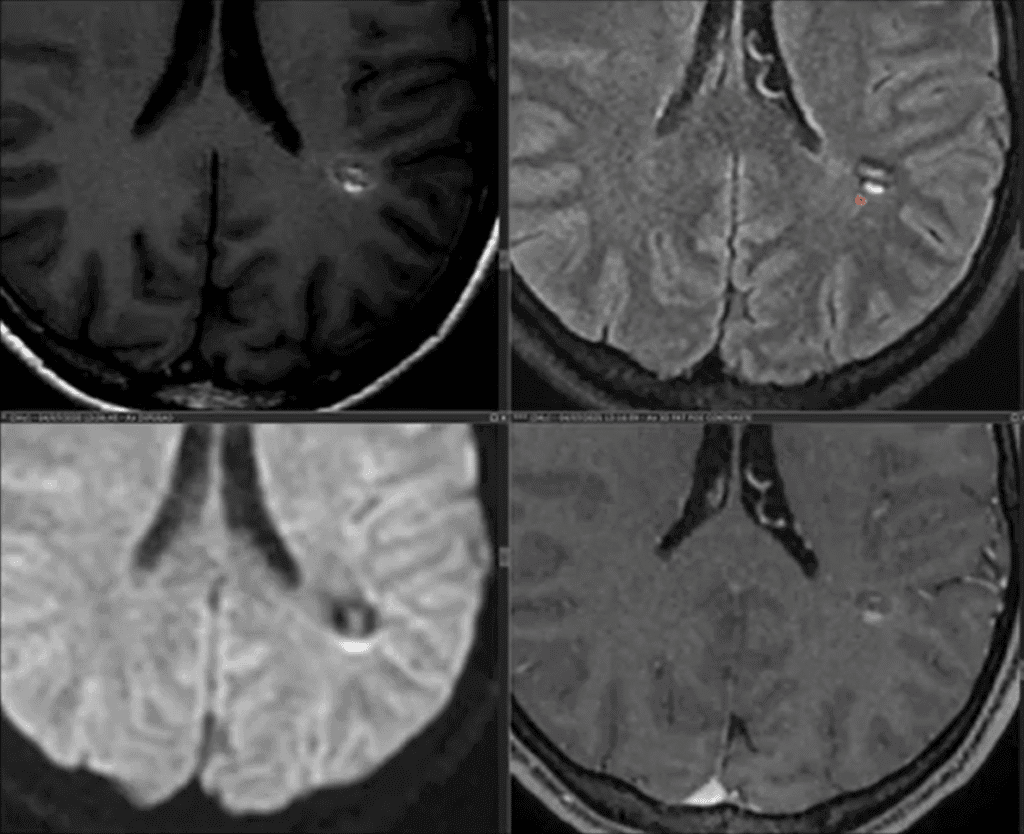

Telangiectasia Capilar: uma apresentação incomum

No vídeo apresentado por Dr. Tomás Freddi, é discutido um caso raro e desafiador de telangiectasia capilar hemisférica, inicialmente confundido com sangramento intracraniano em um…